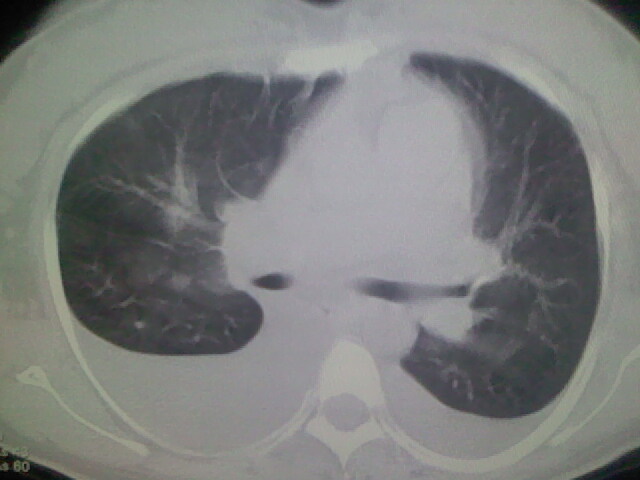

女,24,剖腹产后,突觉胸痛,干咳,不能平卧

胸水 感染 心影增大 肺水肿?

双肺“肺泡性肺水肿” “胸腔积液”!

双侧胸腔积液,肺泡性肺水肿。后纵隔好像有占位。

肝脾大,双侧胸腔积液,双肺水肿,肺动脉[包括远端小动脉],左右心房,左心室增宽,右心室主动脉无明显改变,符合左心功能不全征;;建议除外二尖瓣关闭不全,扩张性心肌病